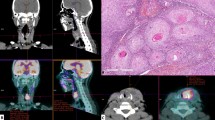

Microvessel structures labeled with CD34 antigen were investigated in all samples (Fig. 1a, b). The area of highest vascularization was chosen at low-power magnification (13.2×) in individual immunohistochemically stained sections. In the selected areas, we calculated the following factors using a image analyzer software (MacSCOPE, Mitani Corp., Fukui, Japan) and graphic soft (Adobe Photoshop 5.0) for Macintosh (BNN, Tokyo, Japan) as previously described by Kamijo et al. [8]. The outlines of the endothelium of each microvessel and of the tumor biopsy specimen are traced on a computer display (Fig. 1c). They were converted to binary images, and the total microvessel number (TN), the total perimeter of the microvessels (TP), and total tumor tissue area (TA) were calculated in each of the 20 cases. TN divided by TA is the TN:TA ratio, and TP divided by TA is the TP:TA ratio.

Image analysis. a Low-power view of hematoxylin–eosin staining showing invasive growth of tumor cells (×13.2). b Immunohistochemical staining for CD34 in SCC biopsy specimens. Note the intense staining of the endothelial cells in these vessels. c The outlines of the tumor and of the endothelium of each microvessel are traced on a computer display. The total number of microvessels and the total microvessel perimeters have been calculated. d The yellow circle indicates the oxygenated area within 150 μm of a microvessel. The ratio of tumor tissue in an area extending beyond 150 μm from the microvessel was calculated as hypoxic ratio in each case

Figure 1d shows the yellow painted area within 150 μm from microvessels. The oxygen diffusion distance in tumor tissue around vessels is ~150 μm, and the ratio of tumor tissue beyond 150 μm from microvessels was calculated in each of the 20 cases (hypoxic ratio, %).

In all patients, the pretreatment FDG-PET images demonstrated an increased uptake of FDG corresponding to the known primary lesion, as compared to that of the background tissues (Fig. 2).

The microvessels in all biopsy specimens were stained with a CD34 antibody. On the computed images, TN:TA, TP:TA, and the hypoxic ratio were calculated; TN:TA = 62.55 ± 34.67 vessels/mm2, TP:TA = 2.86 ± 1.71 mm/mm2, hypoxic ratio = 8.43 ± 8.10% (Fig. 1).